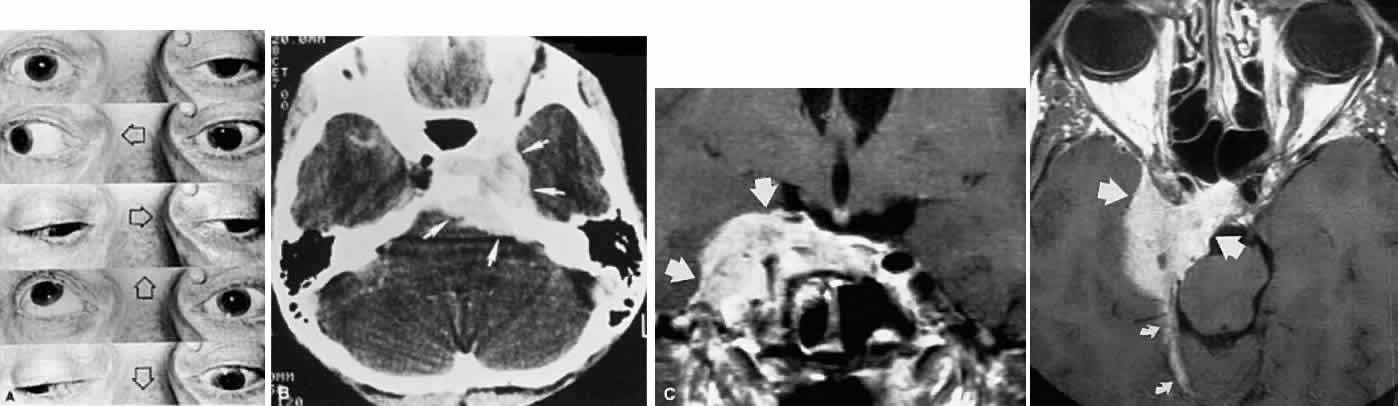

ACUTE INFECTIOUS POLYNEUROPATHY

The bulbar variant of the Guillain-Barré syndrome (Landry ascending paralysis) often presents as a painless, rapidly progressive bilateral ophthalmoplegia. As it evolves, this cranial polyneuropathy may mimic unilateral or bilateral oculomotor palsies, but it usually progresses to a more or less total symmetric ophthalmoplegia that may include the pupils and accommodation. Lid elevators can be normal or minimally involved. The presence of acute or subacute facial diplegia confirms the diagnosis and practically excludes other considerations (Fig. 17).

Commonly, the disorder follows a febrile or “viral” illnesses, or is seen in association with infectious mononucleosis. Although the well-known cerebrospinal fluid protein elevation, in the absence of cellular response, is a sine qua non of this disorder, by no means is this dissociation a constant finding. Detailed nerve conduction studies in one patient with generalized Guillain-Barré syndrome129 revealed that demyelination occurred first in the most distal nerve and progressed to the spinal root; during recovery, remyelination occurred initially at the spinal root level. This sequence may explain the typical interval of days to weeks between onset of symptoms and rise in cerebrospinal fluid protein, which probably increases only when the spinal roots become involved.

In 1956, Fisher130 documented the ophthalmoplegic variant of acute idiopathic polyneuritis, characterized by oculomotor palsies, areflexia, and ataxia. Pathologic material published by Asbury et al131 demonstrated inflammatory infiltration of nerve roots, including peripheral and cranial nerves; these authors proposed that their findings suggest that the polyneuritis syndrome is related to a lymphocyte-mediated autoimmune reaction. The patient studied by Grunnet and Lubow,132 however, showed central chromatolysis in the nuclei of the third, fourth, fifth, and twelfth nerves, and of the anterior horn cells, with only sparse lymphocytic infiltration. Additional clinical evidence that Fisher's syndrome can indeed affect the central nervous system (CNS) includes the following: loss of voluntary saccades with preservation of pursuit; upgaze paresis with intact Bell's phenomenon; internuclear ophthalmoplegia; cerebellar ataxia; hemiparesis; extrapyramidal signs; and disorders of consciousness, including obtundation and electroencephalographic abnormalities.133 Radiologic abnormalities include enhancing midbrain tegmental lesions in a case of bilateral internuclear ophthalmoplegia, vertical gaze palsy, ataxia, and hyporeflexia.134